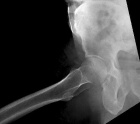

D.R. - 65 year old male, c/o worsening right hip/buttock pain for six months. Pain is constant, worse with activity. Tylenol helps a bit. No F/C or constitutional sx.

PMH: Crohn's disease, nephrolithiasis, prostate infection, gallstones